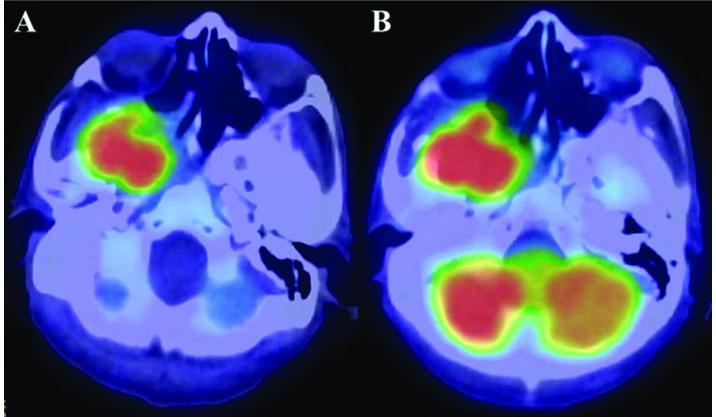

Ameloblastic carcinoma, secondary type, is an extremely rare odontogenic malignant tumor. The present study reports the case of a 58-year-old male with ameloblastic carcinoma that extended into the intracranial space close to the internal carotid artery. Surgical excision was performed, as headaches were being caused via compression by the mass. Small remnants of the tumor remained surrounding the internal carotid artery following surgical resection. Although the remnant tissue was not detected on magnetic resonance imaging or 18F-fluorodeoxyglucose (FDG)-positron emission tomography (PET), it was clearly visualized on C-methionine PET in the early post-operative follow-up period. No neurological deficits were exhibited during the follow-up period, and C-methionine PET was able to detect the remnant lesion distribution in the intracranial space. The current study presents a rare case of ameloblastic carcinoma that extended into the intracranial space. In addition, several diagnostic imaging tools were compared in order to determine the most suitable imaging modality. At present, the patient is continuing a therapeutic course of radiation and evident mass reduction has been observed. However, the therapeutic effects are currently under consideration. To the best of our knowledge, this is the first study on the effectiveness of using C-methionine PET for detecting ameloblastic carcinoma with intracranial extension.

继发性成釉细胞癌是一种极为罕见的牙源性恶性肿瘤。本研究报告了一例58岁男性成釉细胞癌患者,肿瘤已延伸至靠近颈内动脉的颅内空间。由于肿块压迫引起头痛,遂进行了手术切除。手术切除后,颈内动脉周围仍残留少量肿瘤组织。尽管在磁共振成像或18F-氟脱氧葡萄糖(FDG)-正电子发射断层扫描(PET)上未检测到残留组织,但在术后早期随访期间,C-蛋氨酸PET清晰地显示了残留组织。随访期间未出现神经功能缺损,C-蛋氨酸PET能够检测颅内空间残留病变的分布。本研究报告了一例罕见的成釉细胞癌延伸至颅内空间的病例。此外,比较了几种诊断成像工具,以确定最合适的成像方式。目前,患者正在继续接受放射治疗,已观察到明显的肿块缩小。然而,目前正在评估治疗效果。据我们所知,这是第一项关于使用C-蛋氨酸PET检测颅内延伸型成釉细胞癌有效性的研究。